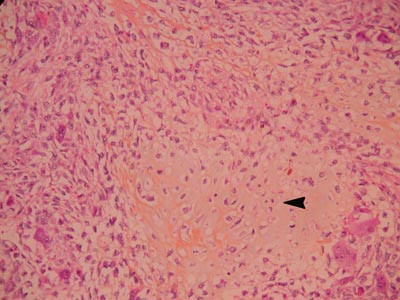

Det peroperative histologisvaret var overraskende og medførte ny gjennomgang av tidligere journalopplysninger. Pasienten hadde ved mammografi i 1998 fått påvist en velavgrenset tumor på 1,7 · 2,5 cm i høyre mamma. Tumor var vurdert som forenlig med fibroadenom. To år senere ble det påvist en stor lobulert tumor ved siden av den tidligere påviste tumoren. Svulstene hadde til sammen en diameter på 5,6 cm. Biopsier fra begge tumorer viste fyllodetumor, men det var usikkert om den var benign eller malign. Klinisk ble det beskrevet infiltrasjon av hud med rubor og forstørrede aksillære lymfeknuter. Det ble derfor gjort ablatio mammae med aksillært lymfeknutetoalett. Histologisk undersøkelse av operasjonspreparatet konkluderte med benign fyllodetumor, fri reseksjonskant og samtidig påvist osteokondroid metaplasi (fig 1). Ingen malignitet var påvist i aksillære lymfeknuter. På grunn av lavt mitosetall og skarp avgrensning ble tumoren oppfattet som benign.

Endelig histologisvar fra lungeresektatet var: «Lungevev med metastase fra høygradig malign fyllodetumor med utbredt kondroid differensiering (primærtumor i høyre bryst). Vekst ut i bronkie og inn i pleura viscerale» (fig 2). Ved utskrivningen fra medisinsk avdeling ble pasienten henvist til Radiumhospitalet for videre oppfølging. Det ble der senere påvist ytterligere metastaser til lunge og columna, og hun fikk palliativ strålebehandling. Hun døde ca. seks måneder etter lungeoperasjonen.